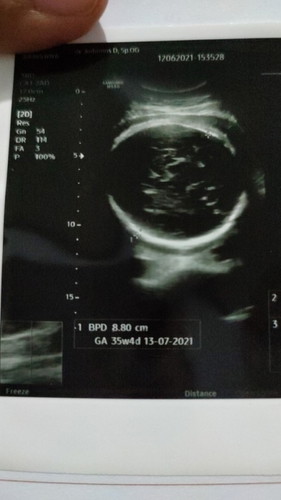

bun, saya ragu sm HPHT sya (25/10/2020) dihitung pskesmas usia skrg brdasarkan hpht 33W4D HPL akhir july/agust 2021 tp setelah sy perhatikan utk USG di dokter dr ukuran janin dll kok di 36W ya tulisanya,posisi pun udh msuk panggul bgt? skrg sya di suruh tes swab sm pskesmas utk jaga2 kalo 2 minggu lg tiba2 brojol bs lgsg tindakan. ada yg seperti itu gk ?#bantusharing #ingintahu #jangandibully #pleasehelp #firstbaby